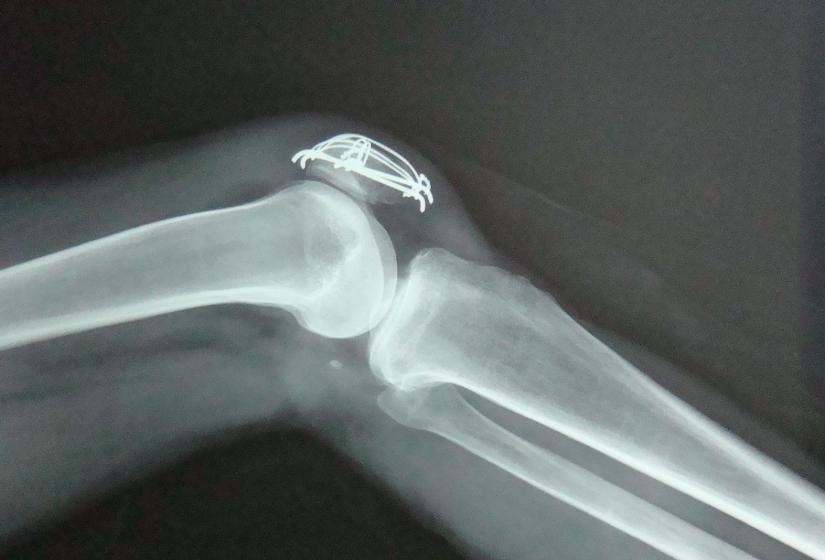

膝盖积水又叫膝盖积液,是一种多发性疾病,其发病部位主要在膝关节。

膝关节是人体滑膜最多,关节面最大和结构最复杂的关节。膝盖积液的背后隐藏着许多关节损伤的情况。一般来说,关节感染、关节有炎症、半月板损伤、滑膜炎等等疾病都有可能导致膝盖积液。

膝关节里有一个封闭的关节腔,关节腔里有少量的关节滑液。

滑液是由滑膜分泌的一种能润滑关节、减少摩擦、营养软骨的透明粘质液体。正常情况下,膝关节的滑液大概在10~20毫升。但如果关节受损、滑膜受到刺激,滑液的吸收和分泌就会受到影响,在关节腔里形成了积液。